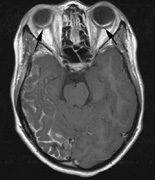

STURGE-WEBER SYNDROME Sturge (1879) reported the case of a child with facial “port-wine stain,” epilepsy, buphthalmos, and a dark choroid.204 Schirmer had noted the association of the facial vascular malformation and glaucoma in 1860.3 Weber (1922) reported brain X-ray findings of parallel streaks (“railtrack” sign), which he interpreted to represent calcific changes (Fig. 19).205

The PWS may not entirely respect the midline, possibly a reflection of transmedian innervation.212 The lesion grows proportionally with the child, often becoming darker in color. 213 The overlying skin may develop nodularity or hypertrophy in two-thirds of patients (by the fifth decade).214 Treatment with a pulsed-dye laser may significantly improve the appearance, but recurrence (i.e., redarkening) is possible.215,216 A deficit in the number of perivascular nerves in port-wine stains suggests that abnormal neural modulation of vascular flow may be involved in their pathogenesis.217 Intracranial leptomeningeal capillary vascular malformation (Figs. 21 and 22) is associated with seizures and contralateral neuromuscular weakness. Central nervous system involvement correlates highly with ipsilateral involvement of the V1 dermatome by a PWS.208,218

It has been hypothesized that the calcific changes reflect cellular anoxic injury secondary to venous stasis/poor drainage.219,220 Abnormal autonomic innervation has also been reported in association with the malformed cortical vessels—innervation only by noradrenergic fibers.221 Studies suggest that the normal increase in brain-blood flow to accommodate increased metabolic demand during seizure activity is blunted in affected brain regions of SWS.222 Thus, seizures in the setting of impaired perfusion may be exacerbating brain injury. Periods of contralateral weakness (days to weeks) can follow a prolonged seizure episode.206,223 When seizures begin early in life, the risk of developmental delay is much higher. In a review of 171 patients with a facial PWS and associated intracranial vascular malformation, 80% were found to have a seizure disorder. Of those, 75% with seizures had an onset during the first year of life, rising to 95% before age 5 years. Nearly all patients had a PWS that included (or was limited to) the V1 distribution. Developmental delay was strongly associated with seizures (71% of children with seizures as compared to 6% without seizures).224 Glaucoma affects 50% to 70% of SWS patients224,225 and it is a therapeutic challenge. From the time of diagnosis, the intraocular pressure, the optic discs, and the corneal diameters need to be measured intermittently, even if an occasional examination under anesthetic is required. The development of glaucoma appears to follow a bimodal age distribution: early-onset/congenital-type and later-onset. The glaucomatous eye is nearly always on the same side as the PWS.224 The highest risk for glaucoma appears to be when the PWS involves both the upper and lower lid: 72% vs. 21% for VI-only (upper eyelid) involvement in one study.224 The bimodal age distribution of glaucoma suggests that more than one mechanism is involved. Angle abnormalities (“trabeculodysgenesis” with or without flat anterior iris insertion) have been reported in association with the early-onset/congential type.225 Other proposed mechanisms include uveal capillary dilation226 and elevated episcleral venous pressure. Reports of blood in Schlemm's canal on gonioscopy support the idea of increased episcleral venous pressure pathomechanics.227,228 Glaucoma in SWS often responds poorly to medical therapy alone. The “trabeculodysgenesis” of early onset Sturge-Webber glaucoma is reported to be similar in gonioscopic appearance to primary congenital glaucoma.229 On this basis, goniotomy was suggested as a treatment of choice in early-onset SWS glaucoma. One group looked at the success of goniotomy, trabeculotomy, trabeculectomy, laser trabeculoplasty and medication in the management of SWS-associated glaucoma.230 In the early onset subgroup receiving goniotomy, median stable interval of intraocular pressure reduction after one procedure was 8 months; with multiple goniotomies and the addition of medical treatment, the median stable interval was extended to 9 years. Other investigators have found that goniotomy alone may be insufficient, requiring filtering surgery at some point. However, trabeculectomy carries a significant risk of choroidal expansion in association with hypotony. Theoretically, the risk may be higher when there is increased choroidal vascularity in association with the facial PWS—a “tomato ketchup” fundus.231 Often, there is associated increased tortuosity of the retinal vessels as well. Placement of a prophylactic posterior sclerotomy prior to filtering surgery to prevent choroidal expansion is controversial.232 Cryo- or thermocoagulation of the ciliary body in combination with medical therapy may be an alternative to surgery.233 KLIPPEL TRENAUNAY—WEBER SYNDROME Klippel-Trenaunay syndrome consists of combined capillary, lymphatic, and venous malformations, in association with varicosities and limb enlargement (Fig. 23). In the majority of cases, the lower limb is affected.234,235